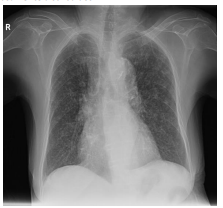

Uma mulher de 40 anos, com sintomas respiratórios e emagrrecimento apresenta alterações em radiografia de tórax,em posição póstero-anterior, compatíveis com padrão miliar (imagem). Em relação a este padrão, considere os itens a seguir.

I. Representam tênues opacidades nodulares agrupadas, de difícil visualização, localizadas nas regiões apicais e axilares

II. Representam opacidade lobar associada a linhas que convergem para o hilo (convergência hilar)

III. Representam micronódulos entre 2 e 3mm de diâmetro difusamente distribuídos

Enunciado 3565667-1

"https://radiopaedia.org/?lang=us">Radiopaedia.org. From the case <ahttps://radiopaedia.org/cases/31375?lang=us">rID: 31375</a>

Está correto o que se afirma em